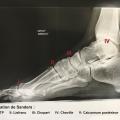

Le plus souvent il s’agit d’une ostéo-arthrite, principalement retrouvée sur les articulations interphalangiennes et métatarso-phalangiennes, liée à un hyper-appui localisé. Plus rarement, les articu-lations du médio- et de l’arrière-pied sont le siège d’une ostéo-arthrite liée à une neuro-arthropathie de Charcot classée Sanders II ou III (fig. 1 ).

Le plus souvent il s’agit d’une ostéo-arthrite, principalement retrouvée sur les articulations interphalangiennes et métatarso-phalangiennes, liée à un hyper-appui localisé. Plus rarement, les articu-lations du médio- et de l’arrière-pied sont le siège d’une ostéo-arthrite liée à une neuro-arthropathie de Charcot classée Sanders II ou III (